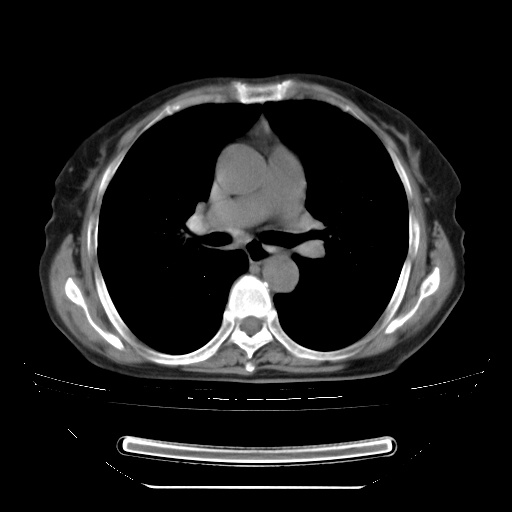

两肺内病灶呈小结节状和树芽状,纵膈的肿大的淋巴结密度不均匀,并见有钙化,考虑为两肺结核可能更大些。

两肺内病灶呈小结节状和树芽状,纵膈的肿大的淋巴结密度不均匀,并见有钙化,多形态病灶,考虑为两肺结核,肝内考虑小囊肿。

考虑两肺播散性肺结核,纵隔淋巴结结核。

片子很好,质量很高,两侧肺门淋巴结肿大并有钙化,两肺弥漫病灶,首先考虑tb并播散,但年龄大了呀(72岁)小细胞肺癌不能除外,如果是肺癌也没什么大的治疗了,建议正规抗结核治疗后复查

纵隔见肿大淋巴结并钙化,首先考虑结核,但感觉小结节像“挂果”征,分布位于支气管边缘,所以不排外肺泡癌,建议抗唠后复查吧?不然是癌的话,也不好治吧?化疗?